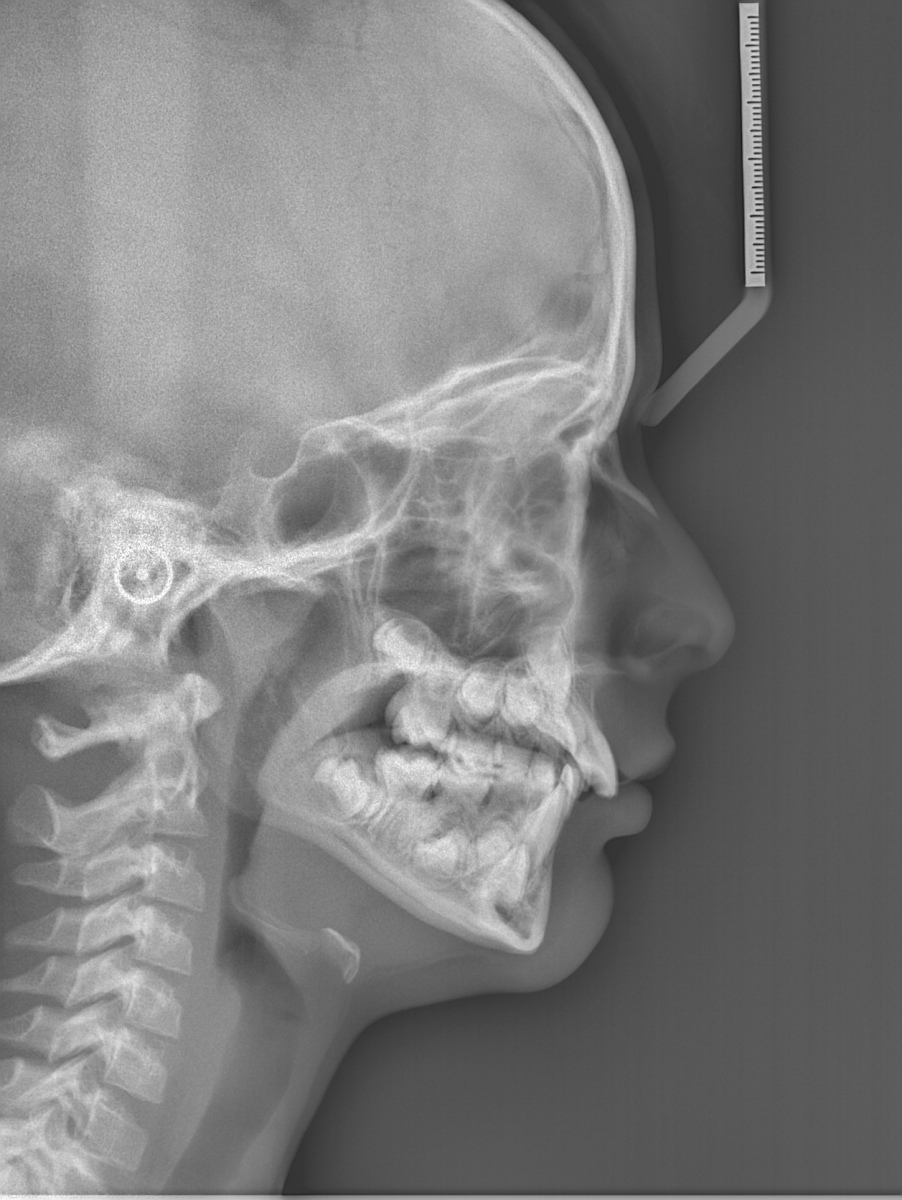

Il nostro studio è inoltre dotato di un a unità radiografica modernissima che permette di eseguire:

• teleradiografie